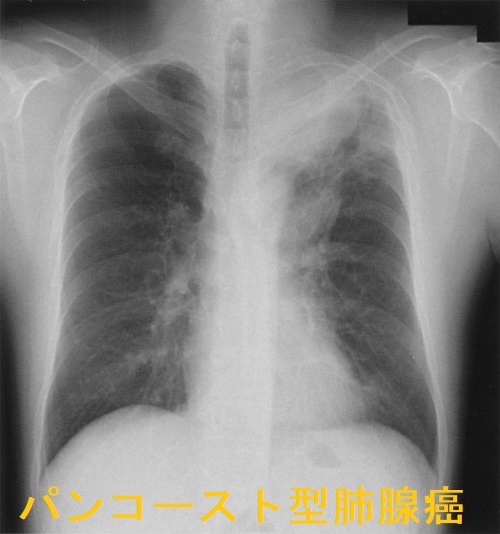

パンコースト型肺癌(Pancoast 型肺癌)は肺尖部浸潤型肺癌で、

- 胸部エックス線にて早期発見難

- 呼吸器症状がない

- 最近は腺癌な割合が増えている